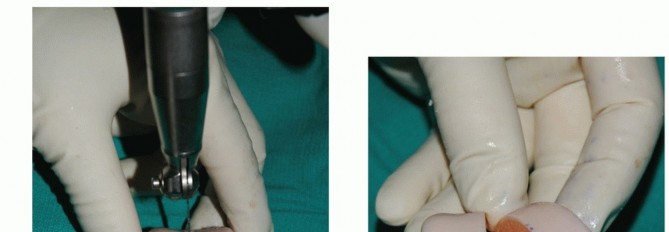

The allograft can be stabilized with two large pointed reduction clamps (TECH FIG 3B).

Extract the graft from the donor talus (TECH FIG 3C).

- TECH FIG 3 • A. The dimensions of the recipient site are carefully recorded and transferred to the allograft. B. Two pointed reduction clamps are used to stabilize the allograft during preparation. C. Donor allograft with newly prepared graft removed.